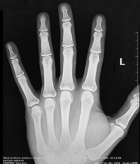

M.C. – 29 year old white male with five month history of left hand pain.

Physical exam demonstrates tenderness to palpation overlying base of 3rd metacarpal, left hand NVI.

Zoom image: Radiological image Radiological image.